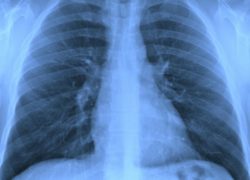

Mesothelioma is a rare form of cancer in which malignant (cancerous) cells are found in the mesothelium, a protective sac covering most of the body’s internal organs. Most people who develop this disease have worked on jobs where they inhaled asbestos particles. Read more…